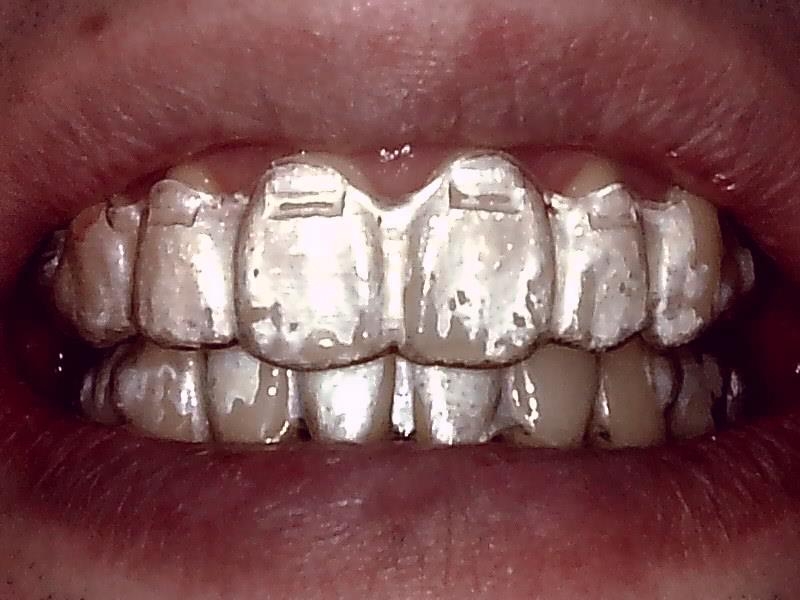

[矯正治療のマウスピース装着]